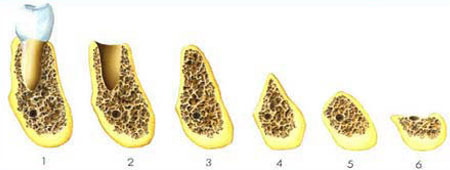

Die Folgen eines Zahnverlusts führen neben der reduzierten Kaufunktion und Ästhetik vor allem zu einem Knochenverlust. Die Ursachen sind in der fehlenden bzw. unphysiologischen Kaukrafteinwirkung. In extremen Fällen kann der Kiefer so weit schrumpfen, dass ein Prothesenhalt nicht mehr möglich ist, und sogar der Kiefer bei extremen Fällen brechen kann.

Mit Hilfe von Knochenersatzmaterialien ist es möglich, den Kieferaufbau nach Zahnentfernung zu unterstützen, bzw. den Knochenabbau aufzuhalten. Allerdings stoßen diese Techniken dann auf Grenzen, wenn eine absolute Kieferkammerhöhung angestrebt wird. In solchen Fällen kommen vor allem körpereigene Transplantate in Betracht.